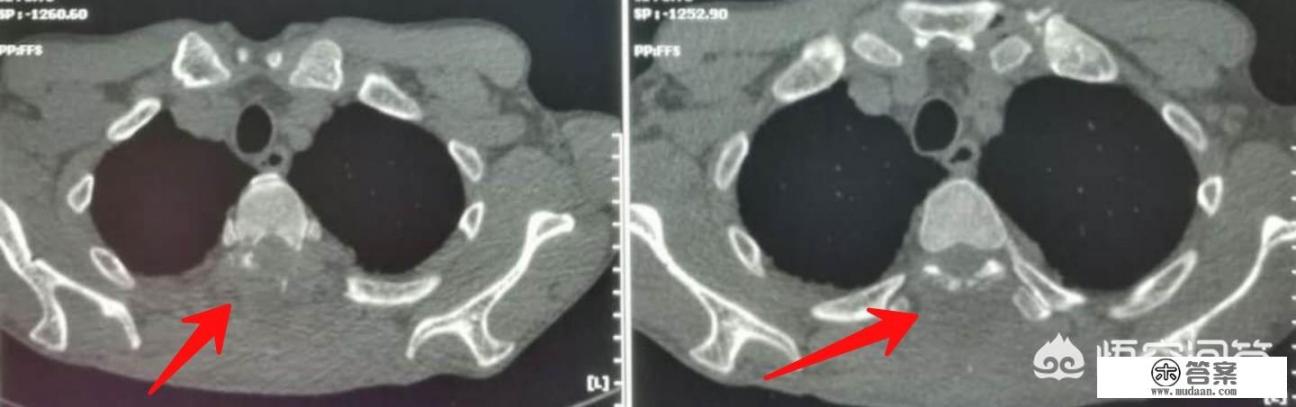

- 肺癌:出现咳嗽咳痰超过一个月要去做胸片检查,为什么这时候提倡做低剂量CT筛查呢?因为很多单位的体检只有胸部正位,很多盲区会导致肺结节或者磨玻璃样原位癌漏检,每年一次的CT筛查能够发现病灶,特别是40岁以上、有吸烟史的人群,每年做一次低剂量CT筛查是非常必要的。